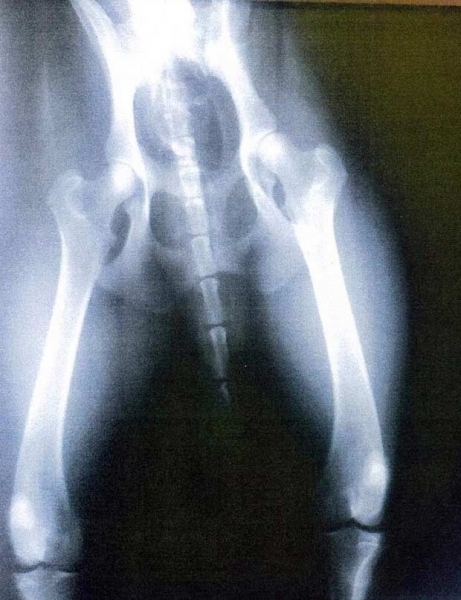

Durante a consulta, ele teria analisado um raio-X de um cachorro, que havia sido entregue pelo policial, e não percebeu a diferença entre a radiografia do cão e a de um homem.